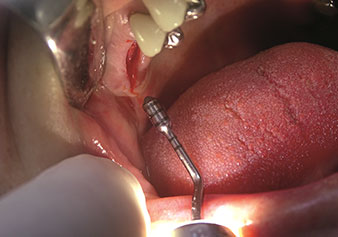

W&H also offers the perfect solution for the internal sinus lift.

Following preparation of the maxillary sinuses with the corresponding instrument set (Fig. 3), the new Z35P instrument (Fig. 4) is used to lift the membrane hydrodynamically. The same instrument set can also be used for piezosurgical preparation of the implant bed in increasing diameters (Figures 3 and 4 included with the kind permission of Dr Mario Kirste, Frankfurt/Oder).

Preparation of maxillary sinus floor and lifting of Schneiderian membrane (Z35P instrument)

Fig. 4: Preparation of maxillary sinus floor and lifting of Schneiderian membrane (Z35P instrument). Photo: © Dr Mario Kirste (Frankfurt / Oder)